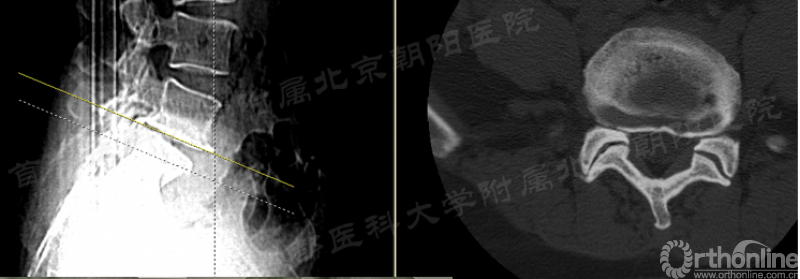

第91例,L2/3节段I-2-a区LDH。在置管后患者诉左下肢屈髋较对侧无力,无下肢放射痛及麻木,术中透视如图(红框)所示。镜下摘除髓核后将工作通道朝向背侧观察神经,患者诉颈部疼痛(脊髓高压症),镜下发现硬膜缺损(红箭头),但神经结构完整。立即结束手术。术后髂腰肌肌力IV级,大腿前方感觉减退,术后复查CT显示L3上关节成型后游离骨块导致出口神经受压。

总结教训:

1、L2/3以上节段穿刺点尽量靠内,不可将工作管道一次性置入椎管;

2、术中患者一旦出现神经症状应立即调整;

3、患者诉颈部疼痛,不是“趴着累了”,应考虑硬膜缺损,脊髓高压,需立即停止手术,必要时对症治疗;

4、在行关节突成型时应警惕尖部骨块游离挤压出口神经的可能性。